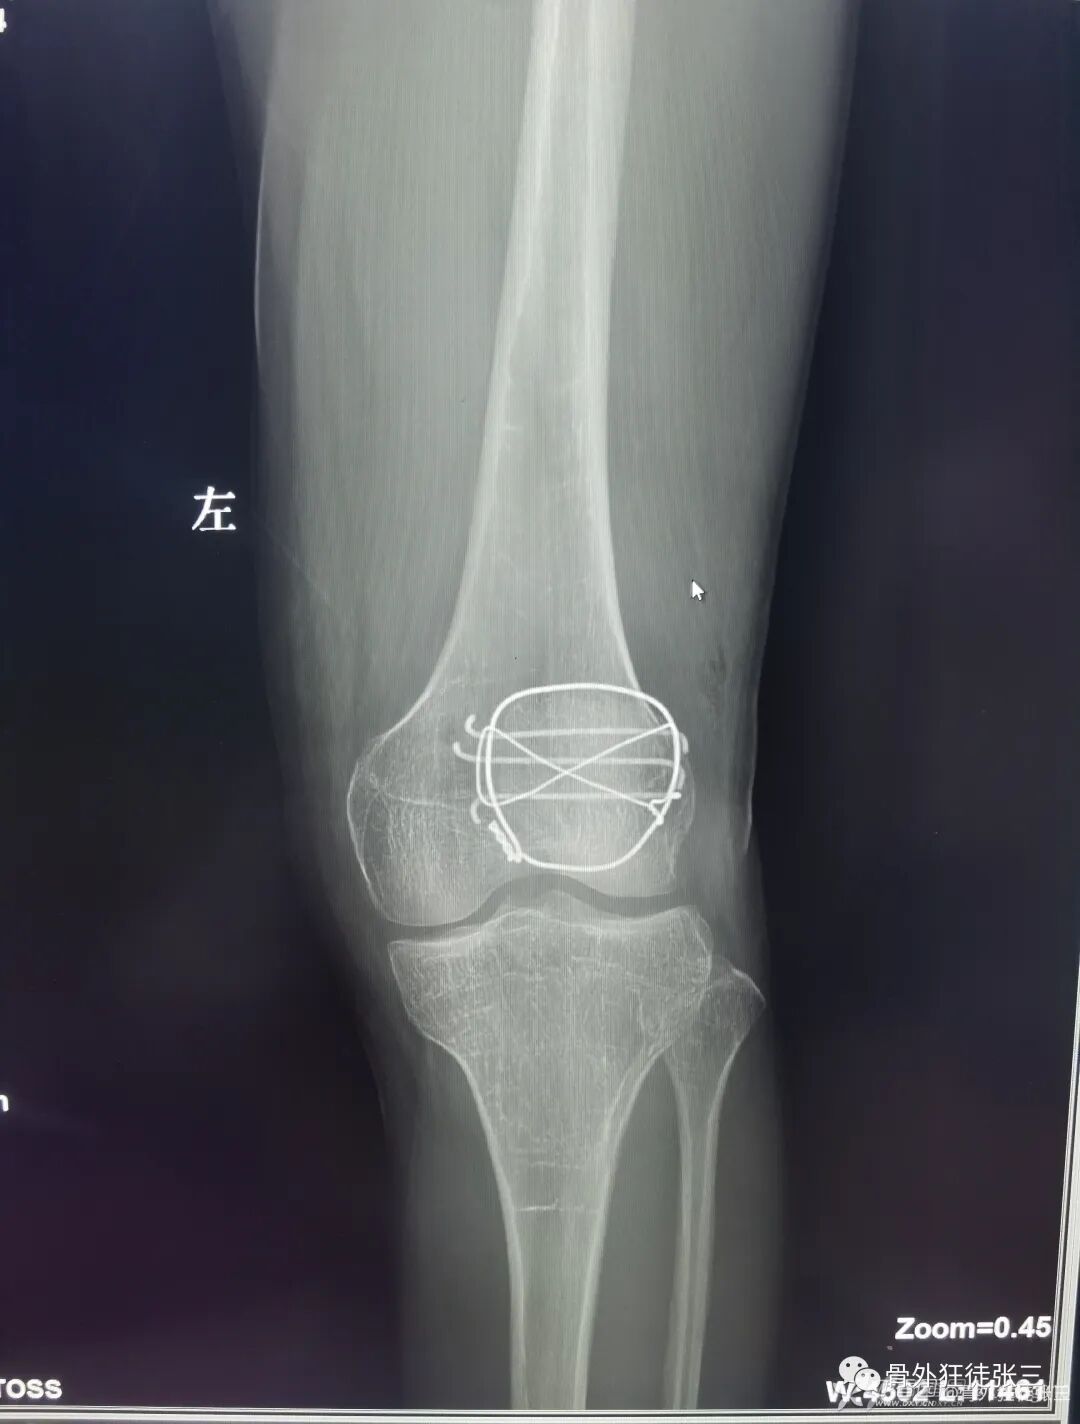

病例28,髌骨骨折,克氏针张力带

病例55,髌骨横行骨折克氏针张力带